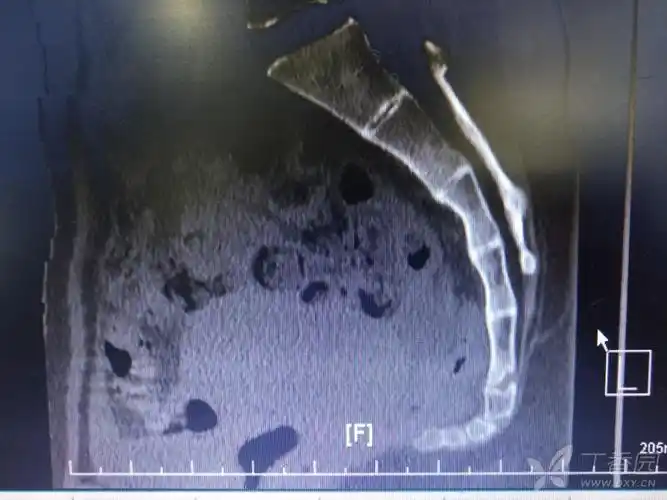

骨折? [病例帖]